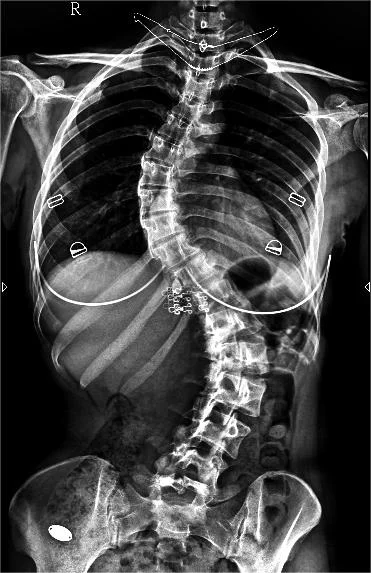

不用再去大醫院排隊等片子! 側彎的角度(Cobb Angle)變化是治療成效的唯一指標。宸新復健科配置專業 X 光設備:

- 即時診斷: 初診當下立刻拍攝全脊椎影像,醫師直接測量角度,判斷是否需要背架或復健。

- 精準監控: 復健每 3-6 個月需重新拍攝,確認側彎是否有惡化或改善。

透過 X 光測量出的柯氏角 (Cobb Angle),決定了我們的治療方針: